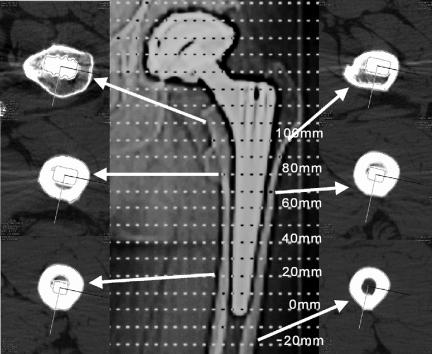

Aseptic implant loosening and periprosthetic bone loss are major problems after total hip arthroplasty (THA). We present an in vivo method of computed tomography (CT) assisted osteodensitometry after THA that differentiates between cortical and cancellous bone density (BD) and area around the femoral component.

Cortical and cancellous periprosthetic femoral BD (mg CaHA/mL), area (mm(2)) and contact area between the prothesis and cortical bone were determined prospectively in 31 patients 10 days, 1 year, and 6 years after uncemented THA (mean age at implantation: 55 years) using CT-osteodensitometry.

6 years postoperatively, cancellous BD had decreased by as much as 41% and cortical BD by up to 27% at the metaphyseal portion of the femur; this decrease was progressive between the 1-year and 6-year examinations. Mild cortical hypertrophy was observed along the entire length of the diaphysis. No statistically significant changes in cortical BD were observed along the diaphysis of the stem.

Periprosthetic CT-assisted osteodensitometry has the technical ability to discriminate between cortical and cancellous bone structures with respect to strain-adapted remodeling. Continuous loss of cortical and cancellous BD at the femoral metaphysis, a homeostatic cortical strain configuration, and mild cortical hypertrophy along the diaphysis suggest a diaphyseal fixation of the implanted stem. CT-assisted osteodensitometry has the potential to become an effective instrument for quality control in THA by means of in vivo determination of periprosthetic BD, which may be a causal factor in implant loosening after THA.